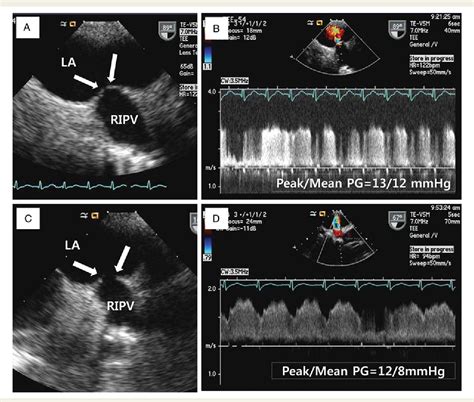

Echocardiogram Uses sound waves to create images of the heart and pulmonary veins, assessing blood flow and detecting any narrowing.

These diagnostic tests help healthcare providers determine the presence and severity of Pulmonary Vein Stenosis, guiding the development of an appropriate treatment plan.